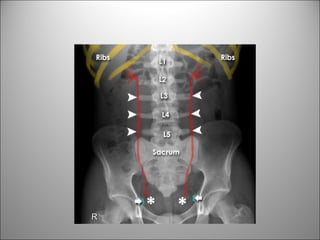

HUESOS

CONTINUANDO CON LA LECTURA

SISTEMÁTICA…